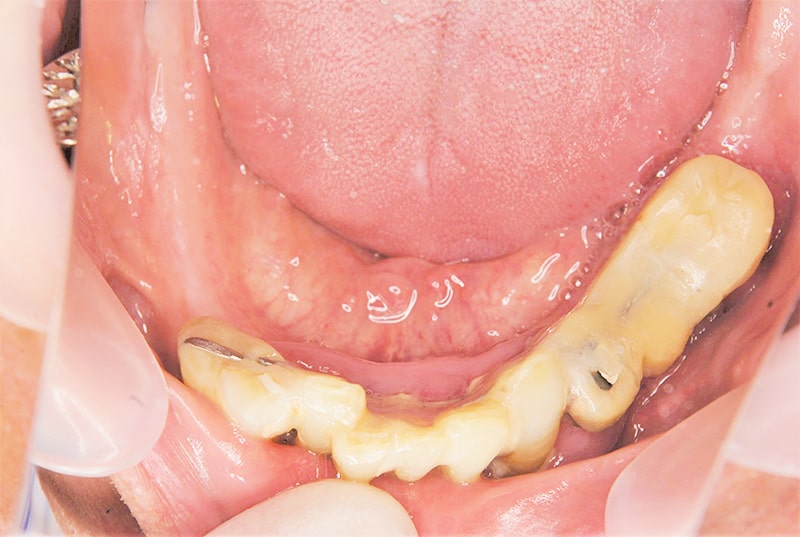

症例2【70代女性】主訴 義歯がわずらわしい・しっかり噛みたい

治療前

治療後(2年経過)

※説明

主訴 上顎のみ部分義歯を使用しているが、入れ歯が煩わしい、固定制のインプラントにして欲しいと来院。

左右上顎第一大臼歯相当は、骨の高さが不足しており、ソケットリフト(骨造成)の必要があり、左右第一小臼歯、第一大臼歯支台のインプラントブリッジを提案。

採血で得られた、CGFメンブレンとAFGブロック(人工骨β‐TCPとAFGを混ぜたブロック)を使用し骨を挙上し、インプラントを埋入。

右下のブリッジも、短根歯で動揺が激しい為に抜歯し、インプラント埋入。

上顎の免荷期間は約4ヶ月、下顎の免荷期間は約2ヶ月を経て、仮歯を装着、リハビリをし、メタルボンド(金属焼付ポーセレン)を装着。

費用 280万(オペ・ソケットリフト・人工骨・採血による濃縮血小板生成・仮歯・最終補綴物まで含む)